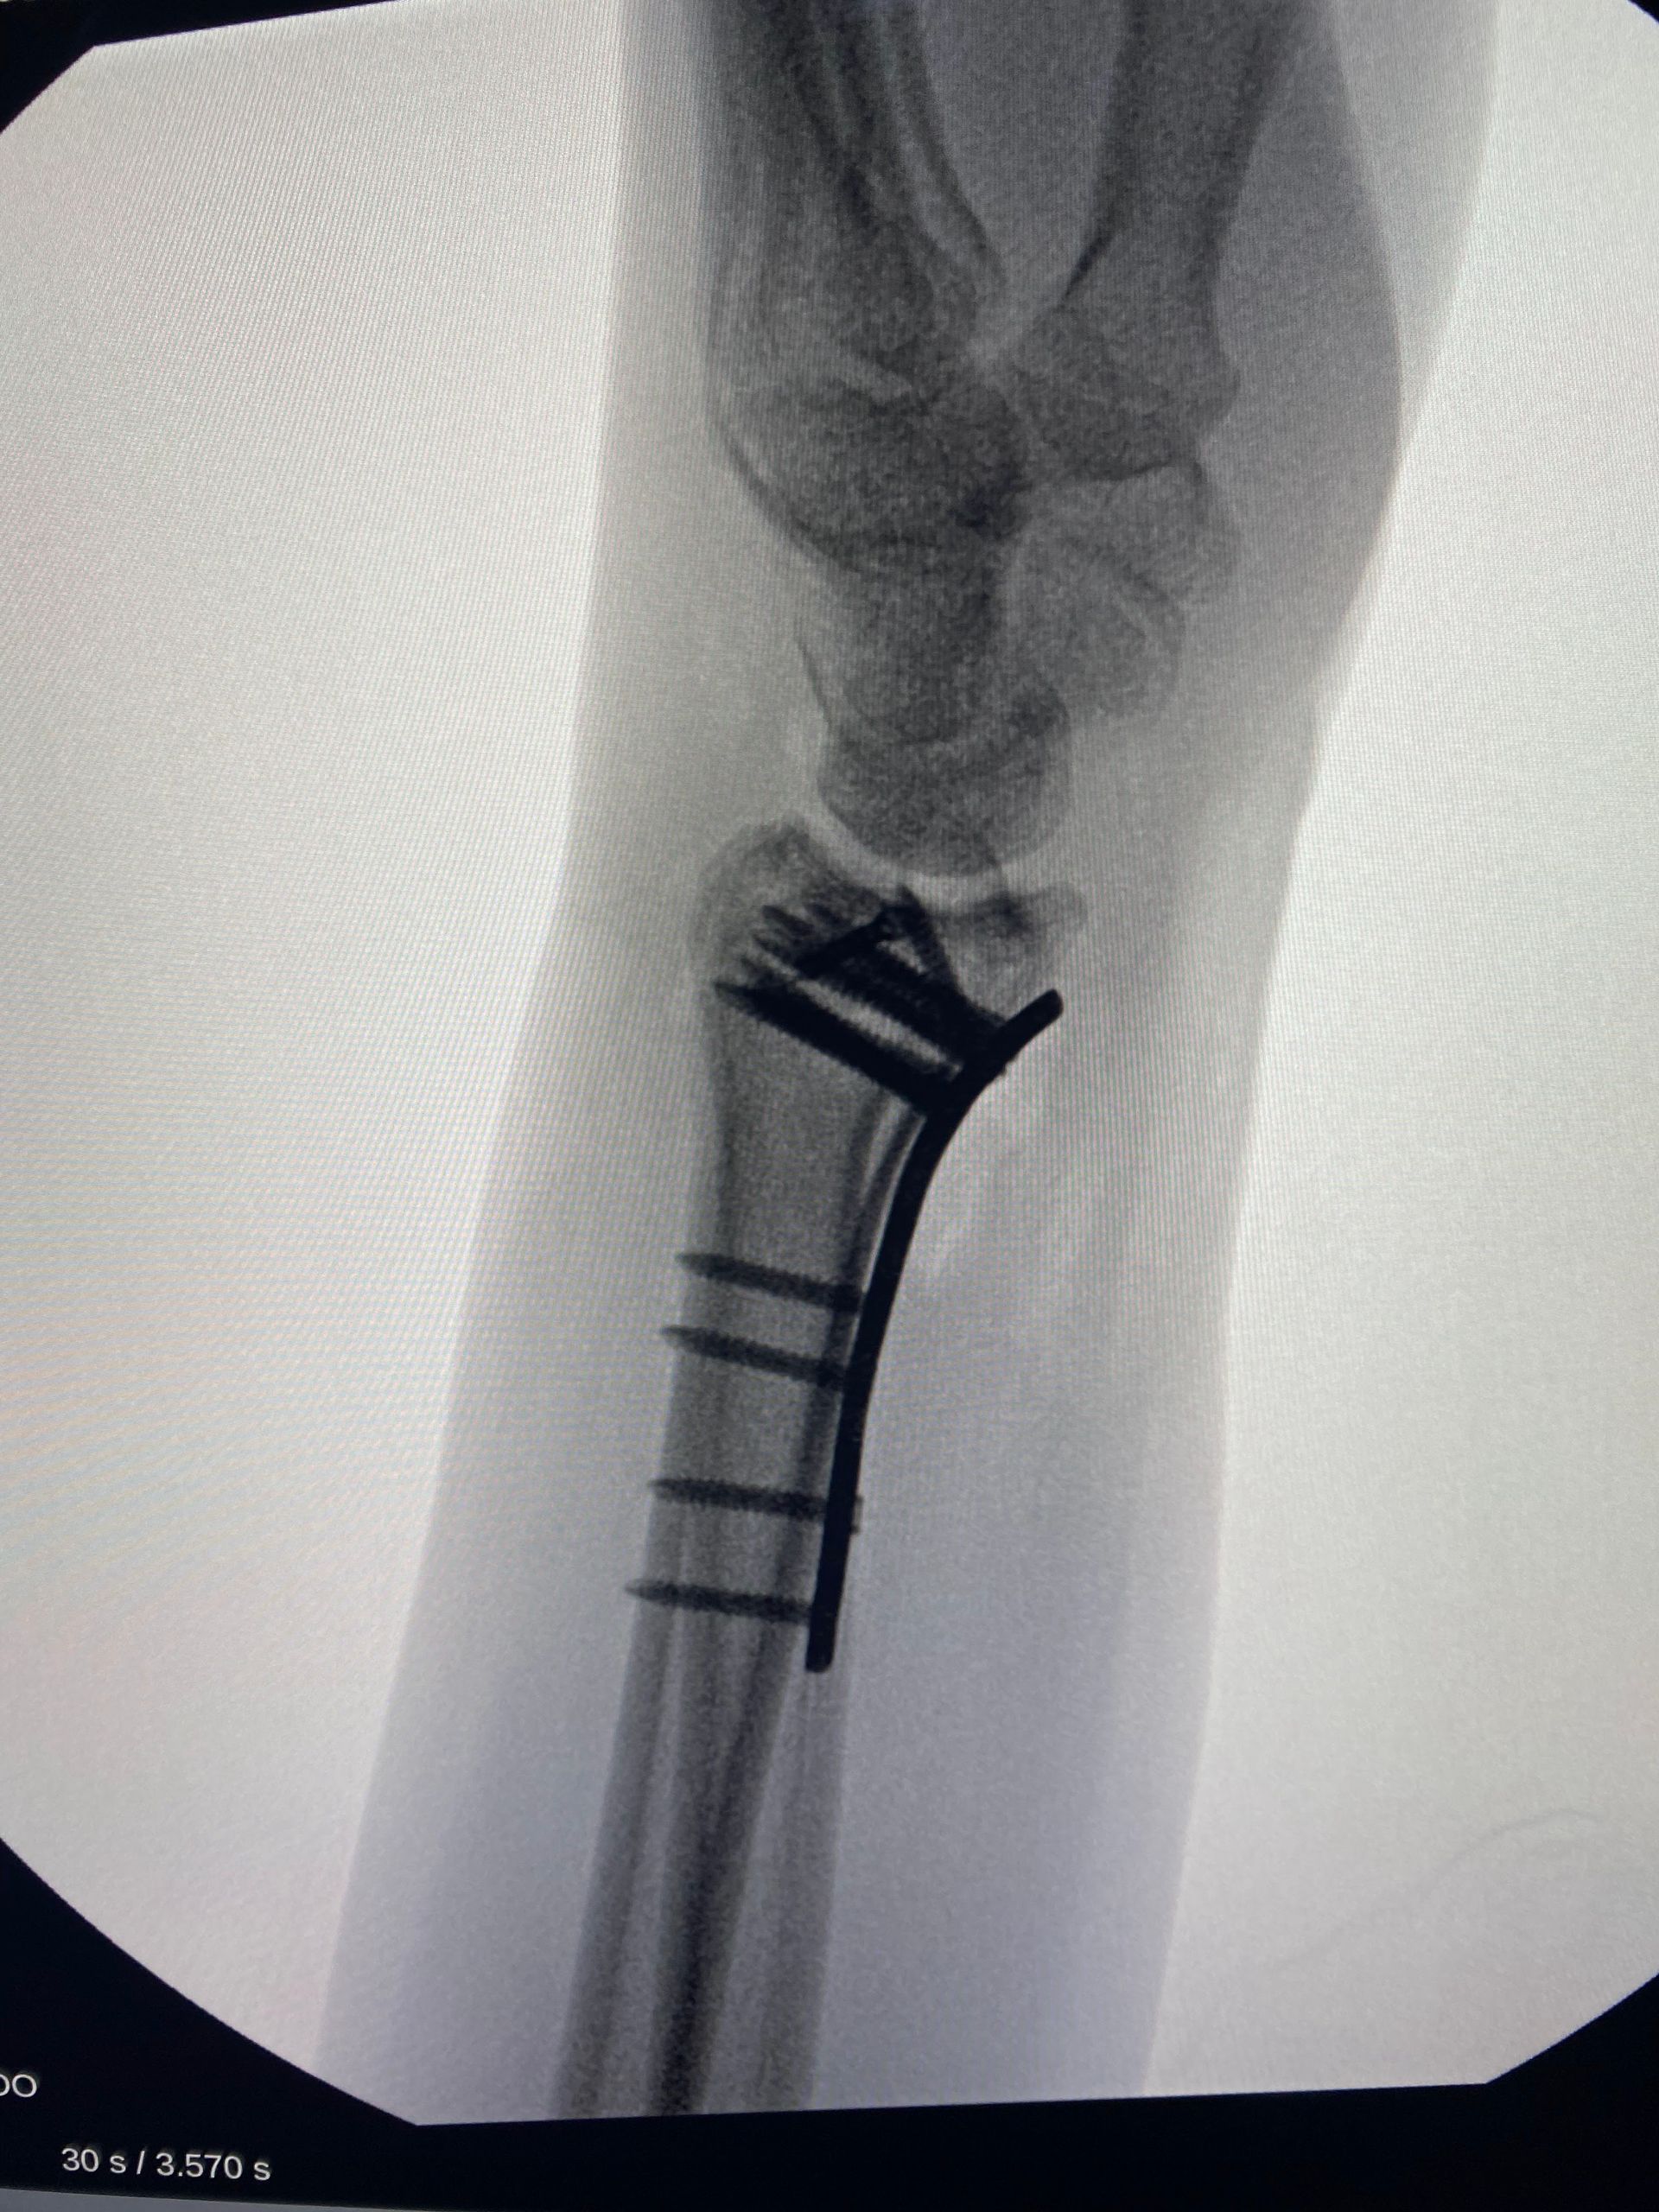

Técnicas cirúrgicas

1) Redução fechada e osteossíntese

a) Fixação percutânea com hastes / pinos

É uma opção ideal para fraturas extra articulares redutíveis de modo fechado (sem necessidade de incisão cirúrgica e exposição do foco de fratura). Pode ser utilizada em fraturas sem cominuição metafisária e quando há boa qualidade óssea.New Paragraph

- O procedimento é realizado no centro cirúrgico, geralmente sob bloqueio anestésico e guiado por radioscopia. Os riscos da técnica incluem lesão de tendões extensores e lesão de nervos sensitivos, particularmente ao inserir as hastes no processo estilóide do rádio.

- A técnica de Kapandji inicialmente descrita como "double intrafocal wire fixation" é muito útil em fraturas extra articulares simples sem cominuição volar. A técnica é muito útil para redução temporária da fratura mas em algumas situações, pode ser utilizada como síntese definitiva. Foi originalmente descrita com uso de 02 fios de Kirschner, um na borda radial e outro a 90° do primeiro. Benoist e Freeland (1995) descreveram o uso de um terceiro fio de Kirschner na topografia da coluna medial.

A) Um fio de Kirschner é introduzido no foco da fratura em direção radial para ulnar. Quando o fio atinge o córtex ulnar do rádio, é utilizado para elevar o fragmento radial e restabelecer a inclinação radial. Um segundo fio é introduzido 90° ao primeiro de modo similar, para corrigir e manter o "tilt" volar. B) Introdução de um terceiro fio de Kirschner, como descrito por Benoist.

2) Redução aberta e osteossíntese

- Placa volar / dorsal

A

placa volar se tornou a forma padrão de tratamento de maioria das fraturas distais de rádio, podendo ser utilizada tanto para fraturas articulares quanto não articulares. Quando bem manuseada, possui a capacidade de manter a redução de fraturas com desvio inicial dorsal, volar ou mesmo com deslocamento radial do fragmento distal.